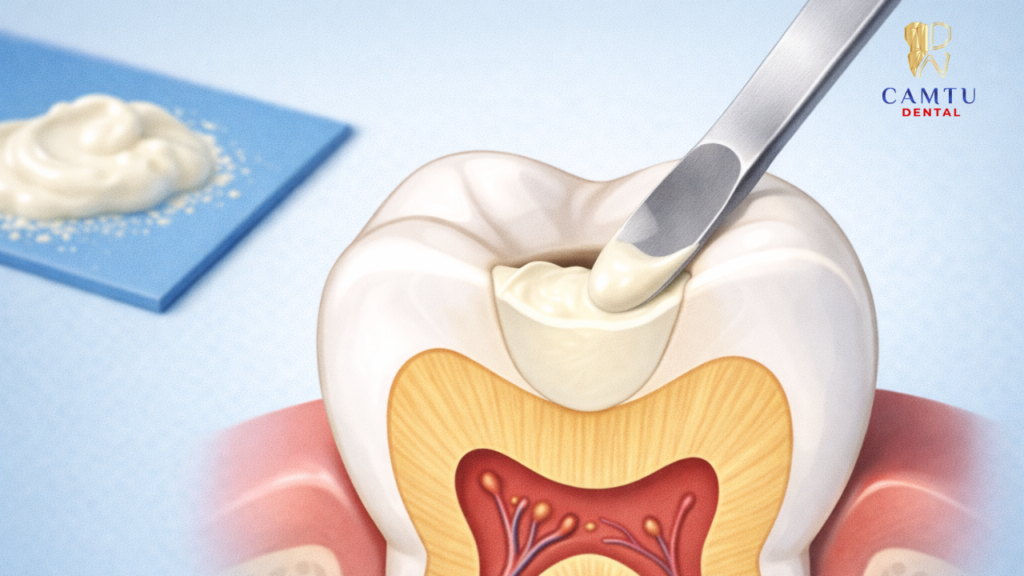

Bước 3: Trám vật liệu GIC

Sau khi vùng răng bị sâu đã được làm sạch và chuẩn bị, bác sĩ sẽ tiến hành trộn vật liệu Glass Ionomer theo tỷ lệ phù hợp. Vật liệu này sau đó được đặt trực tiếp vào vùng răng cần phục hồi để lấp đầy phần mô răng bị mất.

Bác sĩ sẽ tạo hình miếng trám sao cho phù hợp với cấu trúc tự nhiên của răng, đảm bảo khả năng ăn nhai và tính thẩm mỹ. Sau khi vật liệu cứng lại, miếng trám sẽ bám chắc vào răng và giúp bảo vệ vùng răng đã được điều trị.